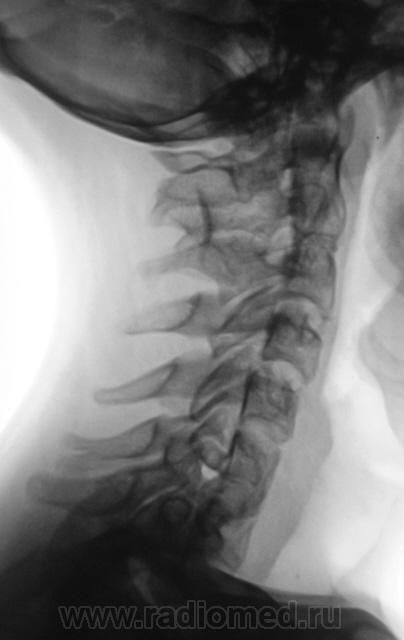

Подросток направлен в рентгеновский кабинет с диагнозом "сколиоз"...

Ну что же, сколиоз есть.

Сколиоз-то сколиоз, но генеза "аномального".

Это синостоз тел верхних шейных позвонков и С6-С7? И боковые клиновидные полупозвонки в верхнегрудном отделе? Это синдром Клиппеля-Файля? А может и Шпренгеля...

Поражает, что только сейчас выявлена такая выраженная дисплазия..там видимо и по органам проблемм хватает..